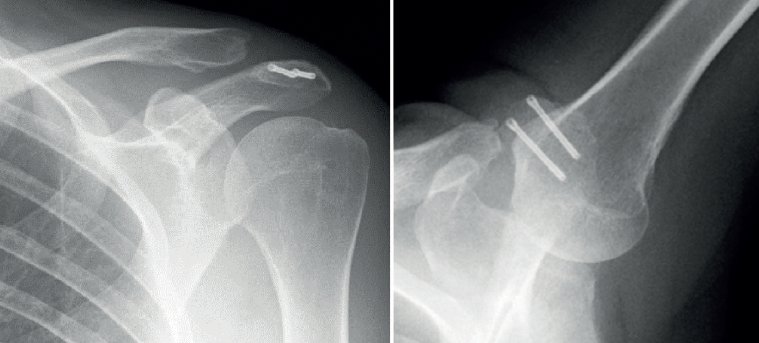

An "8" pattern is preferred, tightened with a sliding knot, manual tension and posterior 8-knot reinforcement, until no loss of tension is observed. This is a modification of the classical technique (19) based on the tension band principle with a 1-mm metal wire in a similar shroud knot pattern (Figure 9). The use of non-metal high-resistance sutures avoids possible complications such as intolerance of the osteosynthesis material, which could require further surgery for removal. Radioscopic control is carried out at the end of the procedure (Figure 10).

Figure 10. Control at the end of the procedure. Posteroanterior and axillary view of the left shoulder.